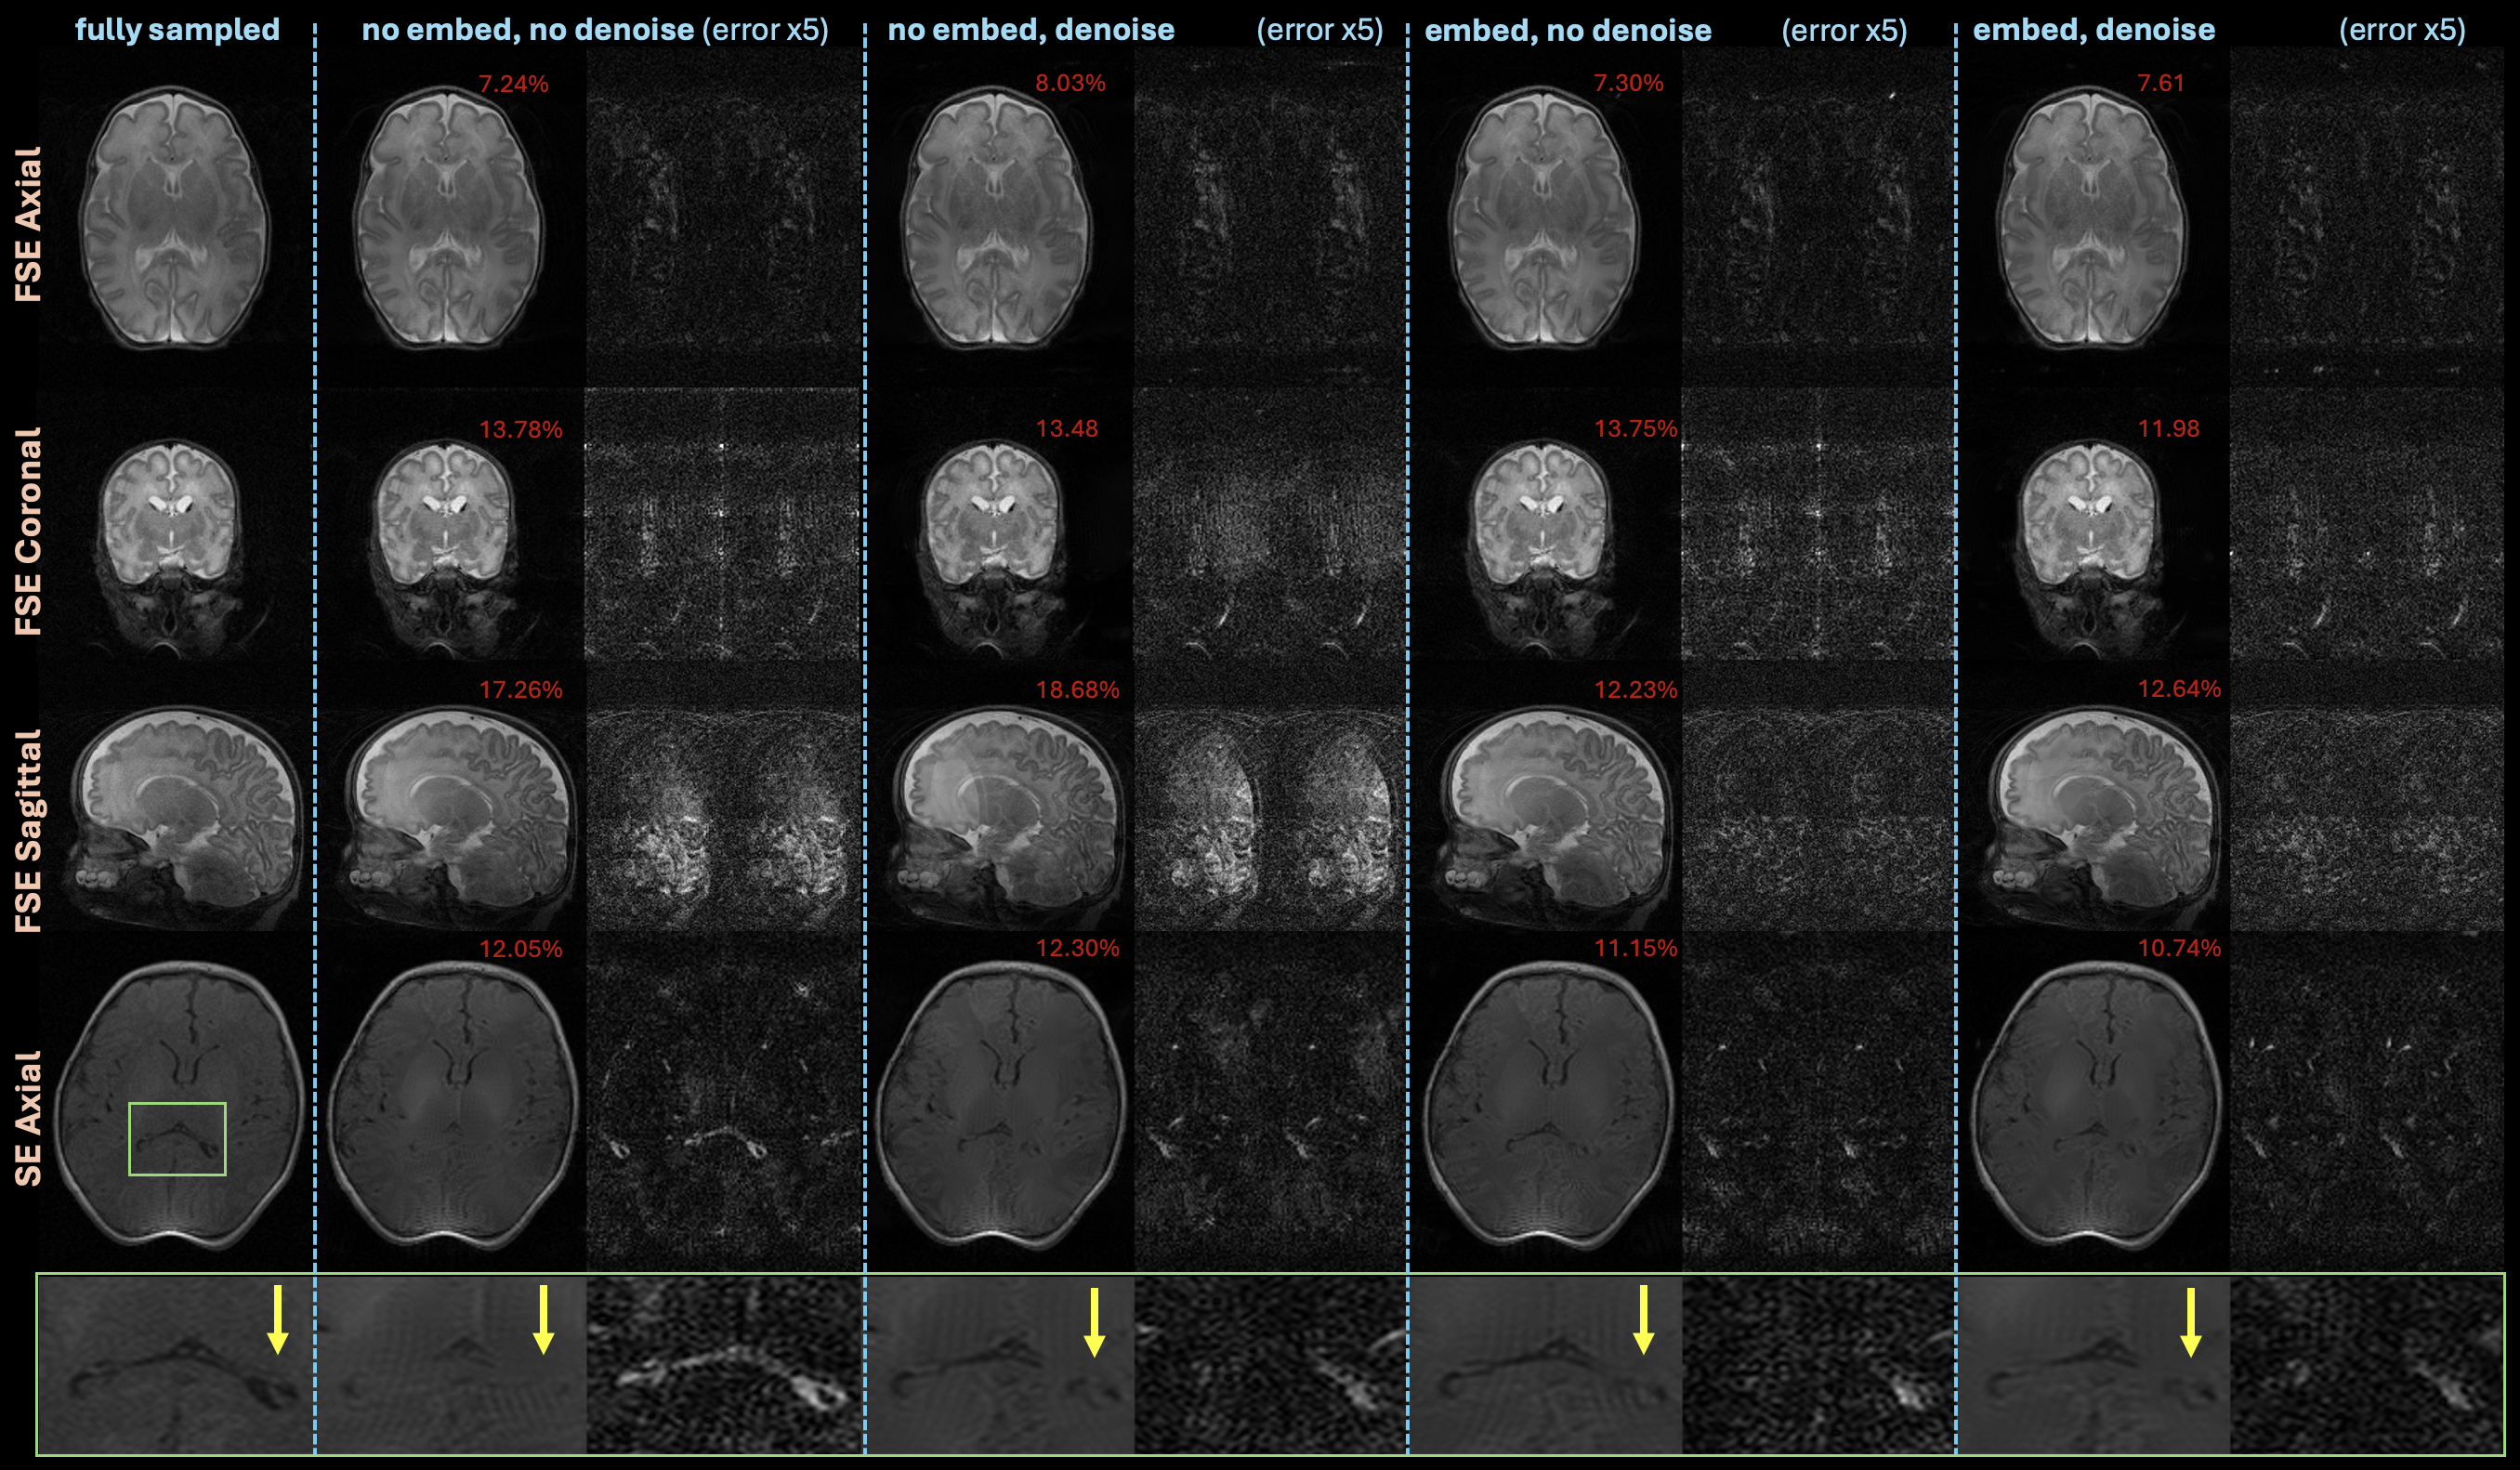

Figure 7 shows violin plots comparing models trained on all data with and without class embeddings and denoising pre-training. In addition, the plots present results at average acceleration rates of 1.5 and 2 with no modifications to the models or posterior sampling hyperparameters. While class embedding improves quantitative performance, denoising does not yield clear improvements. Examples from the test set at are shown in Figure 8. Applying embedding mostly improves quantitative and qualitative performance, but a similar trend is not observed with denoising. However, in the SE results, and its associated zoomed in row, the no embed, no denoise model achieves lower NRMSE than the no embed, denoise model, but suffers from increased hallucination artifacts, particularly in the ventricles, highlighted by the zoomed in panels.

Figure 7: Violin plots comparing NRMSE across the dataset of posterior sampling reconstructions on 1.5x and 2x under-sampled data using diffusion models trained on all data with an ablation on using class embeddings and denoising. While incorporating class embeddings improves performance, denoising does not always yield quantitative improvement.

Figure 8: Example reconstructions from the experiment comparing posterior sampling reconstructions on under-sampled data using diffusion models trained on all data with an ablation on using class embeddings and denoising. In the SE axial results row with zoomed in images, notice how no embedding without denoising yields lower NRMSE than with denoising, but suffers from increased hallucinations.